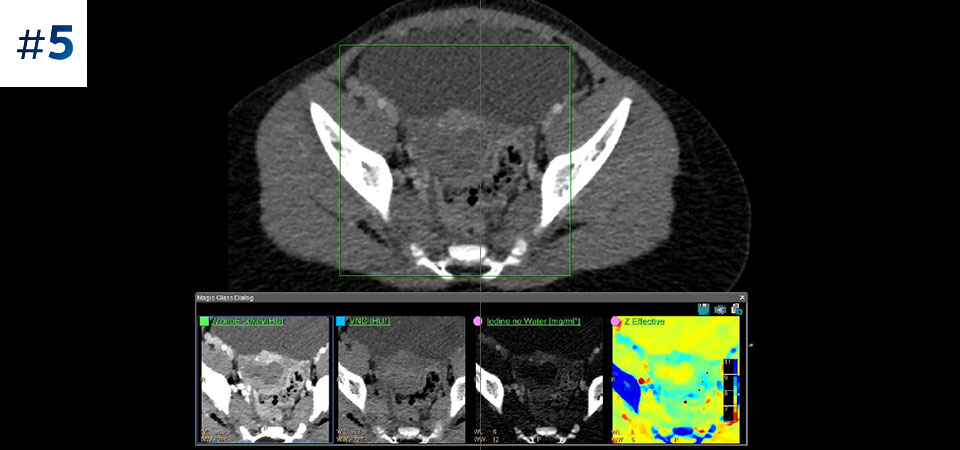

Go beyond conventional CT. See how layers of spectral-detector results can enhance your diagnostic confidence.

See the difference between spectral-detector CT and conventional CT